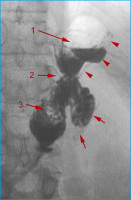

AGB

Abbildung 6: Bandleck nach AGB: Partiell kontrastiertes Magenband (Pfeil) nach Anspritzen des Bandsystems. Breitflächiges Leaking am Bandrand (Pfeilspitzen).

Keywords: GastroenterologieMagenbandRadiologie